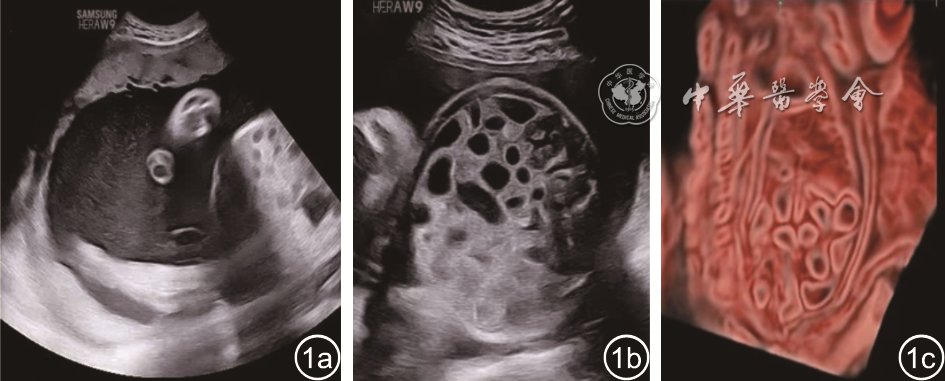

图1 先天性失氯性腹泻胎儿超声图像。图a为产前超声示羊水深度8.3 cm,内见密集的漂浮光点,类似果冻样回声;图b为产前超声示胎儿空肠和回肠广泛扩张,充满液体,肠壁回声强;图c为三维水晶成像见肠腔呈蜂巢状